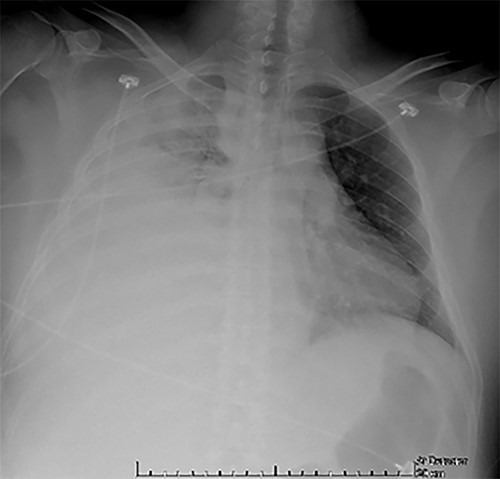

Examination revealed tachycardia, tachypnea, jaundice, dehydration, jugular vein distension, right lung hypoventilation, ascites, upper abdominal tenderness and bilateral lower limb edema. Laboratory workup highlighted neutrophilic leukocytosis, with WBCs exceeding 20 000/μl, along with an abnormal hepatic function panel. The latter showed hypertransaminasemia with ALT predominance over AST (344.7 U/L and 288.5 U/L, respectively), hyperbilirubinemia (10.01 μmol/L) and elevated values of ALP (909.1 U/L) and DHL (709.9 U/L). Of relevance, creatinine elevation (2.11 mg/dl), thrombocytosis (629 × 109/L) and positive D-Dimer (5780 ng/ml) were also noted, so acute kidney injury management and thromboprophylactic measures were initiated. A chest X-ray (CXR) showed a massive right pleural effusion (Fig. 1) and an abdominal ultrasound (US) revealed hepatomegaly with a right nodule (Fig. 2). After further evaluation, tomographic evidence of a right pleural effusion occupying 100% of the lung (Fig. 3) and a 20 cm hypodense, nodular lesion in the right liver (Fig. 4) were identified. These findings were suggestive of an ALA concomitant with an empyema. The patient was admitted into the intensive care unit and prepared for surgery.

Abdominal US at admission: nodular lesion in the right liver lobe.